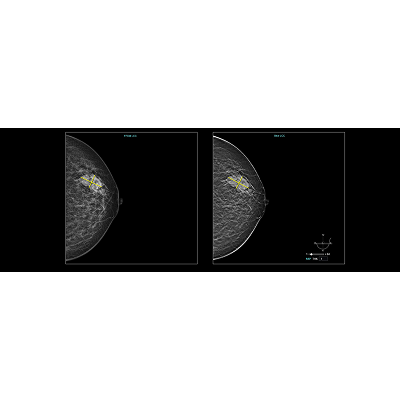

基于最新BI-RADS分类,联影智能DBT乳腺智能分析系统能够自动评估乳腺腺体密度类型,精准检出肿块、钙化、结构扭曲和不对称四大常见病灶,并提供病灶的详细信息,还能够自动生成BI-RADS分类和报告文本,既降低漏诊率,也显著减轻医生的工作负担,使其更专注于诊断本身。